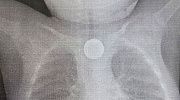

Спасательную операцию осложняли возможность обледенения и шквалистый ветер, но профессиональные пилоты и сотрудники территориального центра медицины катастроф РБ смогли эвакуировать мужчину. Пациента доставили в больницу, сейчас его состояние оценивают как стабильное.